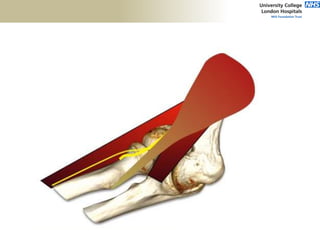

FABS MRI